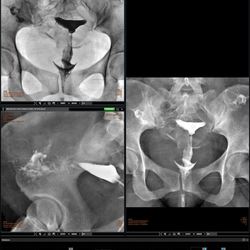

Histerosalpingografía

Manipulación mínima de pacientes politraumatizados.

Posibilidad de realizar estudios de pie de miembros inferiores y composicion de huesos largos.